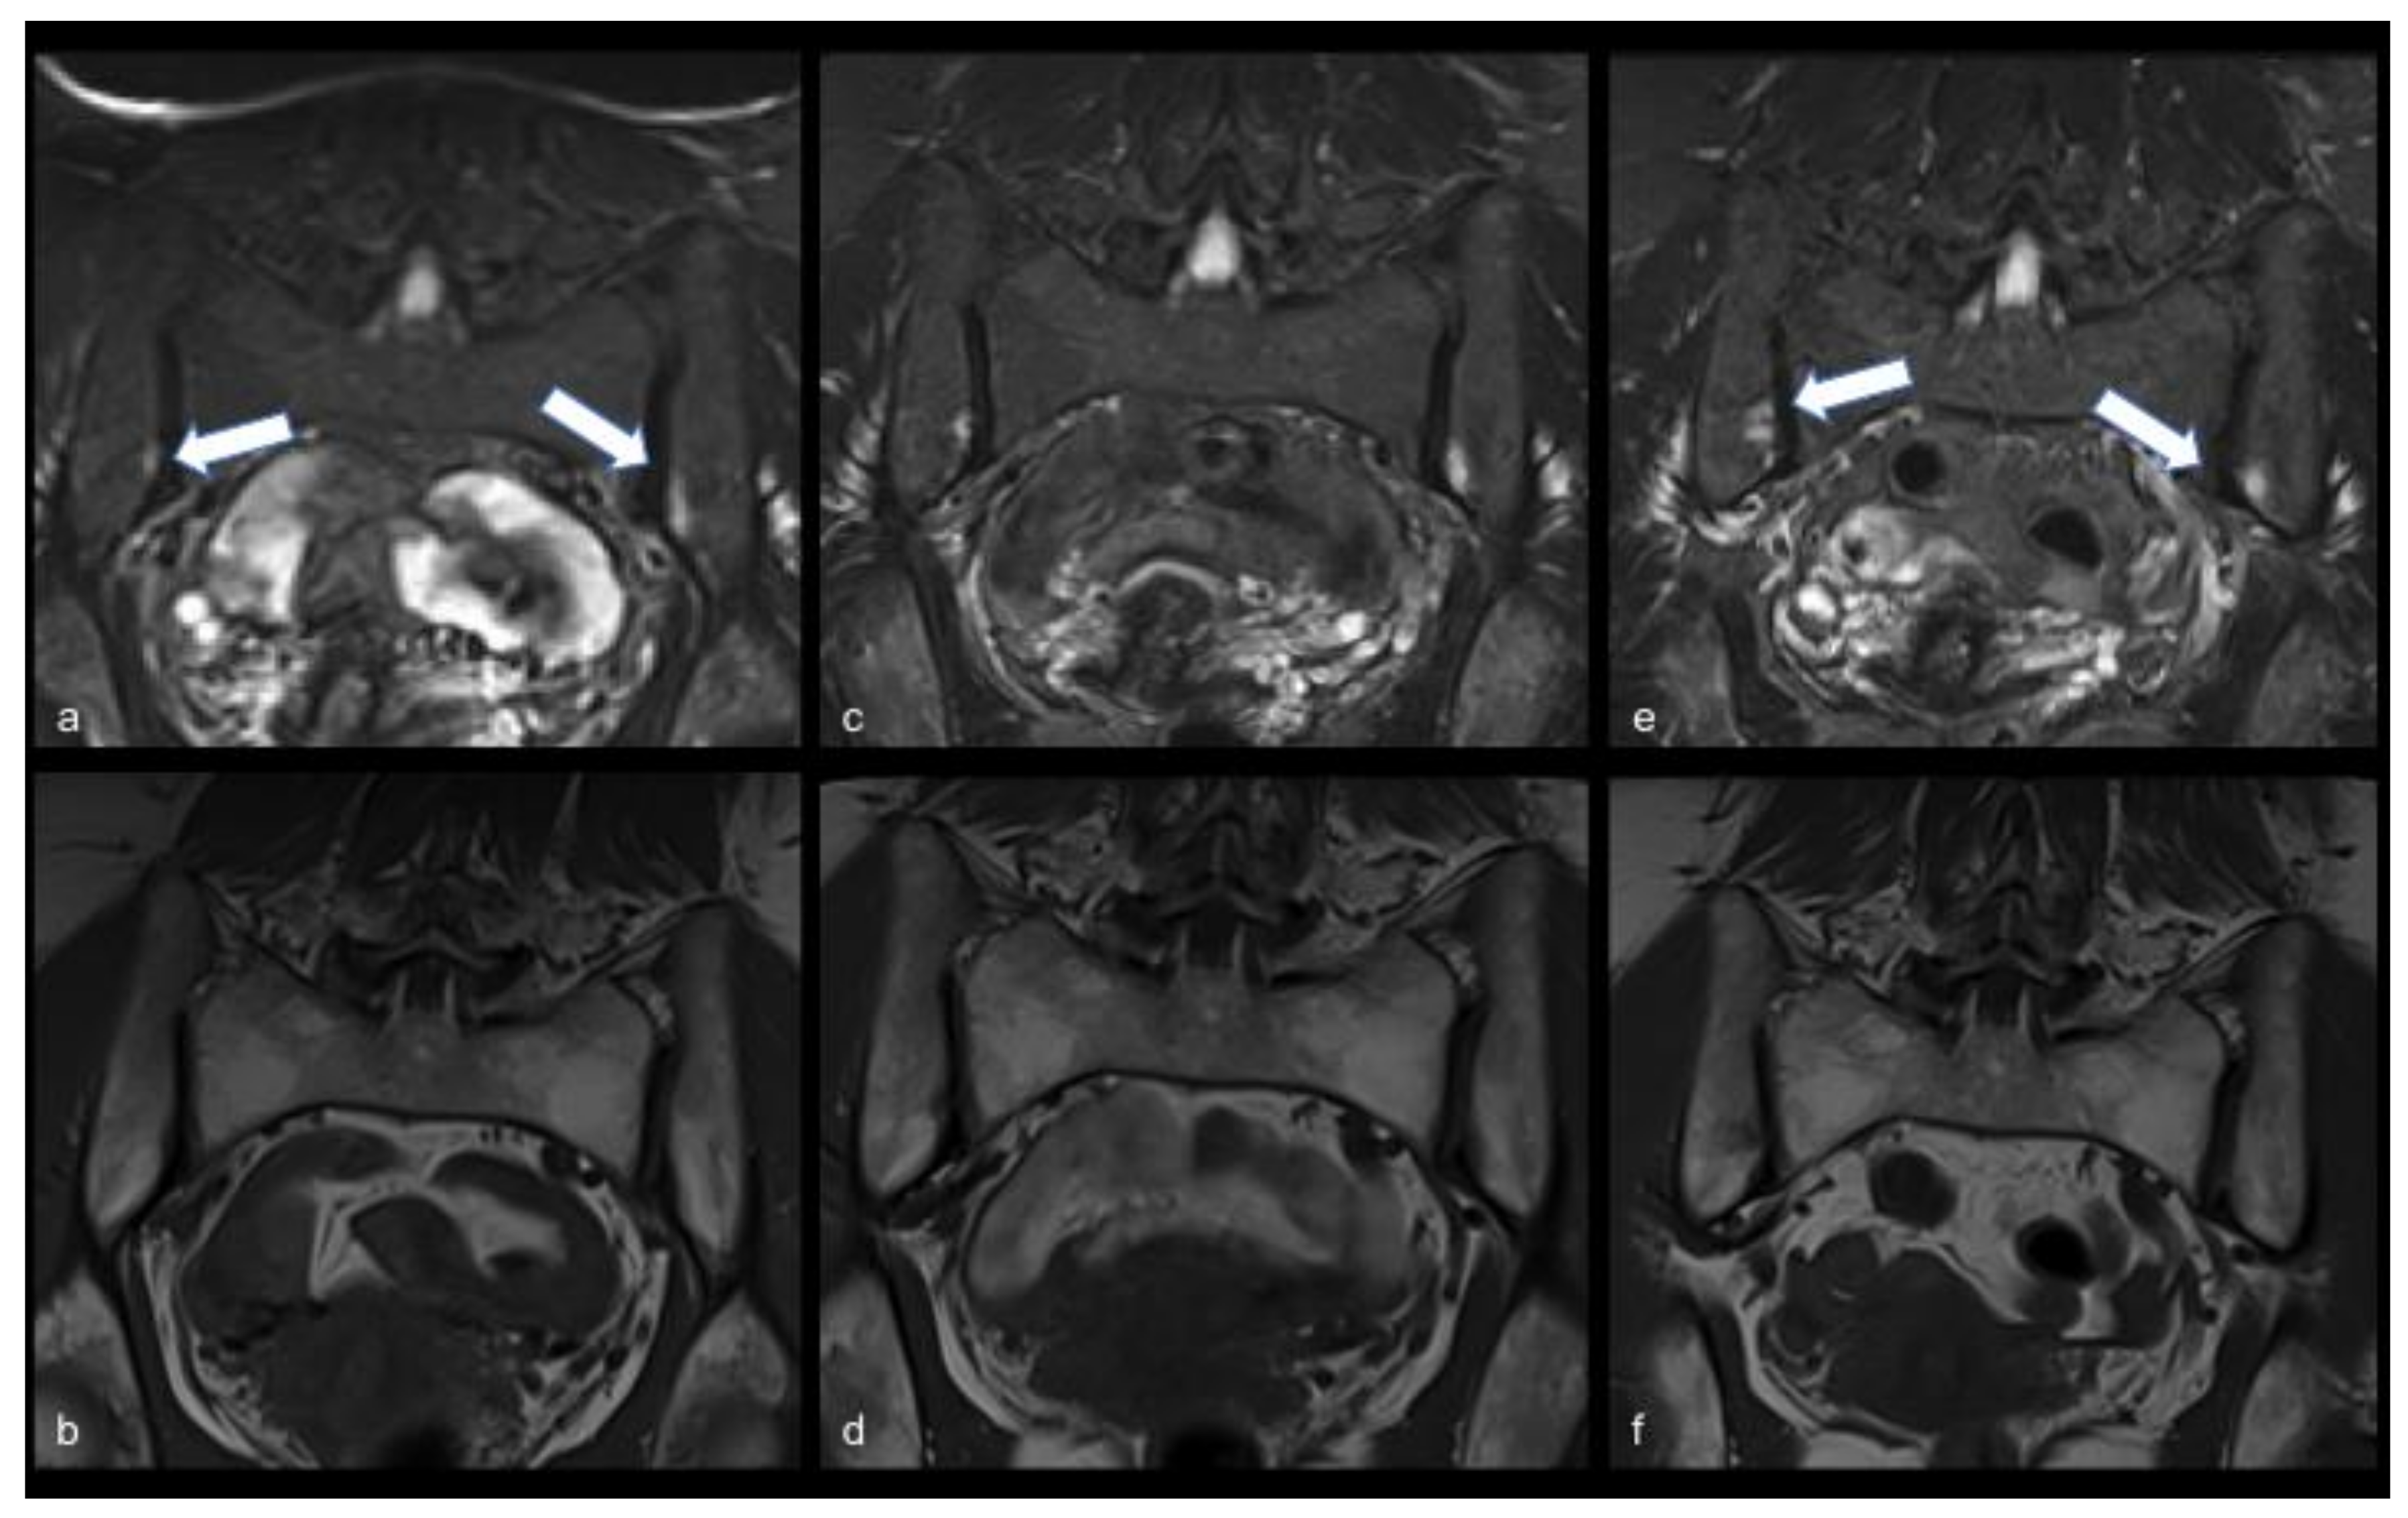

| First MRI | June 2020, bilateral sacroiliitis | June 2020 unilateral sacroiliitis |

| Second MRI | July 2020, bilateral sacroiliitis | July 2020 unilateral sacroiliitis |

| Third MRI | January 2021, bilateral sacroiliitis | February 2021, unilateral sacroiliitis |